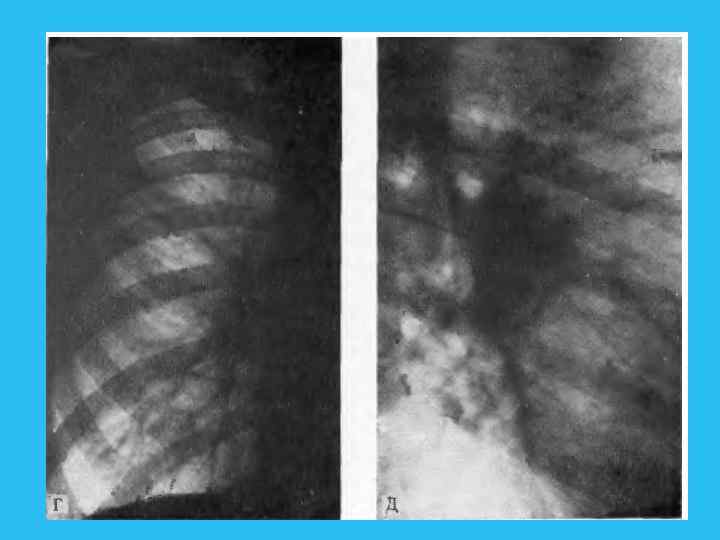

Четвертая фаза соответствует выраженной клинической и достаточно демонстративной рентгенологической картине заболевания. В этот период отчетливо виден опухолевый узел, иногда достигающий нескольких санти метров в диаметре. Связь узла с бронхом и прогрессирующий рост в сто рону последнего приводит к сужению просвета II степени и развитию обтурационной эмфиземы. Нередко при сравнительно быстром метастазировании опухоли в лимфа тические узлы видимая тень в легком представляет собой отображение первичного опухолевого узла, слившегося с метастатически измененными увеличенными лимфатическим узлами (рис. 244). При этом опухолевый узел в корневой зоне часто приобретает полициклические контуры. Обна ружение увеличенных трахеобронхиальных и паратрахеальных лимфати ческих узлов иногда приводит к неправильной расшифровке видимой кар тины, когда все изменения связываются с системным поражением лимфа тических узлов легкого и средостения. По мере развития болезни растет первичный опухолевый узел и стадия гиповентиляции, а затем клапанного вздутия, сменяющаяся ателектазом. Развитие ателектаза может привести к потере изображения опухолевого узла на фоне спавшегося сегмента или зоны. Возникновение ателектаза, так же как и при эпдобронхиальной опухоли, способствует развитию ряда осложнении, о которых уже говорилось. Наступает пятая фаза течения опухолевого процесса. При переходе от экспансивной к инфильтративной фазе роста опухоль начинает распространяться по ходу бронхов и сосудов, что находит своеотражение на рентгенограммах. При этом узел теряет свои четкие очерта ния, появляются грубые тяжистые тени, расходящиеся от опухолевого узла в легочную ткань (рис. 245).

Рис. 245. Ателектаз язычка. Узел в корневой зоне отчетливо не виден. а — прямая рентгенограмма; б — бокивая томограмма; опухолевый узел в корневой зоне отчетливо не виден; в — томограмма. Позиция PS (45°). Опухолевый узел обрастает все разветвления верхне долевого, язычновогои промежуточного бронхов.